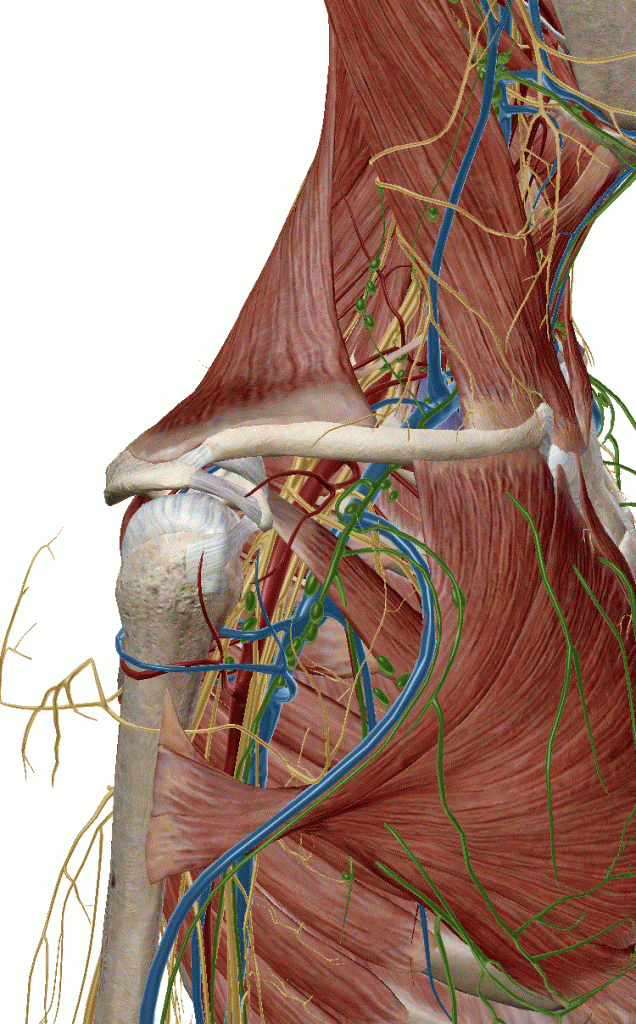

Echographie Sous-clavièreJugulaireFémorale JUGULAIRE G FEMORALE Dt MorissonKohlerDouglas Sous-clavièrePleural J’aime chargement…